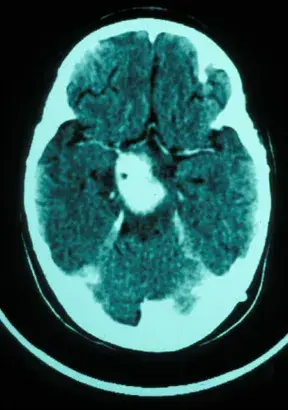

医生,孩子刚才还好好的,突然就哭喊着说自己头痛,好像下一秒就要痛晕过去了一样,你快救救他!急诊室内的一幕令众人纷纷侧目,一位神色慌张的母亲正搀扶着她年幼的儿子,而这竟差点...

一年多前,10岁的安格因呕吐被查出第四脑室肿瘤,在接受分流术后的第5天,安格被再次推入手术室,成功全切了肿瘤,病理报告显示为低级别胶质瘤。然而安格一家看似有惊无险的治疗之路,...